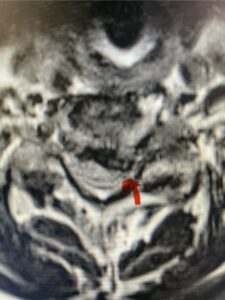

In this next case, this patient is a 47 year-old female who presents with intractable low back pain with severe pain, numbness, and weakness in the right lower extremity that had gotten progressively worse over a year. The patient had failed conservative management including physical therapy and epidurals. She was noted to have ⅘ weakness of plantar flexion. MRI demonstrated a large right L5-S1 disc herniation with severe compression of the descending right S1 nerve root (Fig 3). It was decided to perform a right L5-S1 hemilaminectomy for removal of the disc fragment and decompress the S1 nerve root. When you expose the disc, one must be certain to release any anterior adhesions to the nerve root in order to prevent a dural tear during retraction of the nerve root. It is also important to make sure during exposure and you finally encounter the dura after removing the ligamentum and fat, to make sure you are looking at the nerve root and not the main trunk of the thecal sac because if you don’t you can avulse or damage the nerve root if you retract the wrong structure.

Fig. 3a: Sagittal and axial T2-weighted lumbar MRI images demonstrating large right L5-S1 disc herniation (red arrows)

We found a massive subligamentous herniation which had to be revealed by having your partner retract the freed nerve root with a nerve root retractor and putting slight downward pressure on the more medial and anterior disc space. There is nothing more satisfying when the jelly (disc fragment) of the annulus (donut) comes squirting out and you remove a large chunk of disc material that clearly was stretching the ligament membrane and compressing the nerve root. This does cause back pain in addition to radiculopathy not only by the component of mechanical compression but also the stretching of the nerves within the ligament. We performed this surgery and noted that the nerve root was a very angry red color or hyperemic and we removed a large subligamentous fragment. The patient had improvement of her preoperative radicular symptoms.